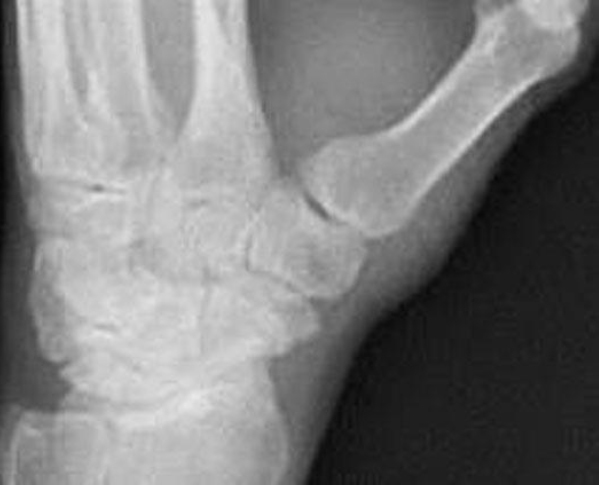

A 53-year-old woman comes to the office because of pain of the dorsum of the left wrist and thumb for the past 3 months. The patient reports that pain occurs with activity. Physical examination shows pain is increased with passive wrist ulnar deviation with the thumb held in the palm and during resisted extension of the thumb metacarpophalangeal (MCP) joint. Axial loading of the thumb does not reproduce pain. An x-ray study is shown. Which of the following is the most likely diagnosis in this patient?

The correct response is Option B.

Pain in the dorsal radial aspect of the wrist can be caused by a variety of conditions; a thorough history and physical examination are key to elucidating the correct diagnosis. In the scenario presented, the patient has a positive Finkelstein test along with reproduction of the pain with resistance to the extensor pollicis brevis muscle. These are classic findings of de Quervain tenosynovitis. The patient’s physical examination points to the first dorsal compartment of the wrist as a source of pathology rather than basal joint or scaphotrapezial arthritis. Radiographs have not been shown to correlate with symptomatology in basilar joint arthritis. Intersection syndrome is a tendinopathy between the intersection of the tendons of the first and second dorsal compartments. The pain of intersection syndrome is generally found more proximally in the forearm and is also increased with resisted wrist extension. Digital flexor tenosynovitis or trigger finger is an inflammatory tendinopathy of the flexor pollicis longus tendon and pain is generally reproduced with resisted thumb flexion.